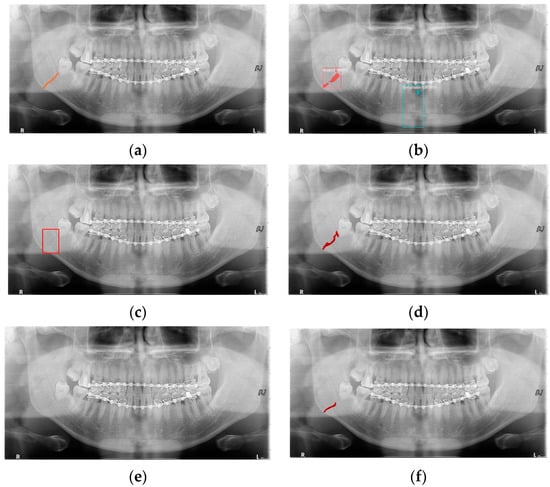

Deep learning networks such as Mask R-CNN, YOLOv4, and U-Net have been used to detect mandibular fractures using only panoramic images. The advantages of the three networks can be identified experimentally through panoramic mandibular fracture images. First, Mask R-CNN specifically marks the fracture area; however, it also marks fractures in areas that are not fractured, such as dark shaded areas in the panoramic image or gaps between teeth; therefore, the false diagnosis rate is higher than that in other deep learning networks. In YOLO, the location information for the six classes divided into anatomical structures is helpful to detect mandibular fractures. However, there are some undiagnosed fracture areas, other than the fractures of the condyle and coronoid process with clear characteristics and location. Unlike the above two deep learning networks, U-Net performs training by labeling fracture and panoramic images. When creating training fracture labeling data, the dislocated fracture area of the condyle fracture is difficult to label. Unlike YOLO, the side fracture area is weak, causing an increase in the misdiagnosis rate when learning by labeling a dislocated fracture. In Figure 17, the mandibular fracture detection results images of LAT YOLOv4 and U-Net with LAT YOLOv4 are compared. The panoramic images in the first and second rows demonstrate the advantages of YOLO and U-Net. While YOLO detects condyle dislocation fractures well, it does not detect angle fractures; however, U-Net detects angle fractures well. The panoramic images in the third and fourth rows show that the undiagnosed area is reduced by using U-Net for the angle area that the LAT YOLOv4 module does not diagnose. Because U-Net performs semantic segmentation, it is advantageous for the segmentation of fractures spread over a wide area. Consequently, the undiagnosed case in the middle of the mandible, where LAT YOLOv4 is weak, is somewhat supplemented by the U-Net module.

Figure 17.

The comparison of LAT YOLOv4 and U-Net with LAT YOLOv4 detection results. (a) LAT YOLOv4 (with red boxes), and (b) U-Net & LAT YOLOv4 (with red boxes and lines).